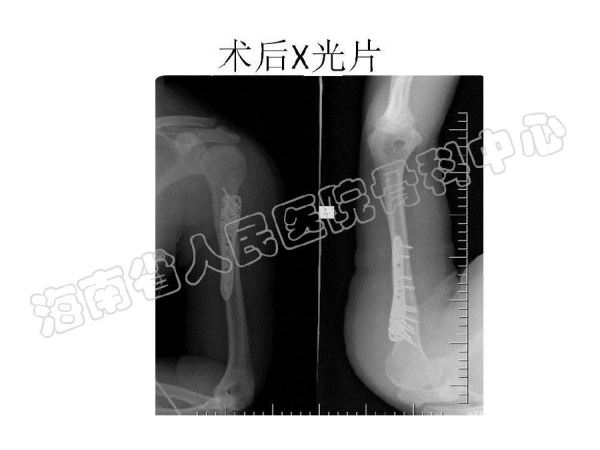

2014-04-14 文章来源:海南省人民医院骨科中心 沈宁江 我要说